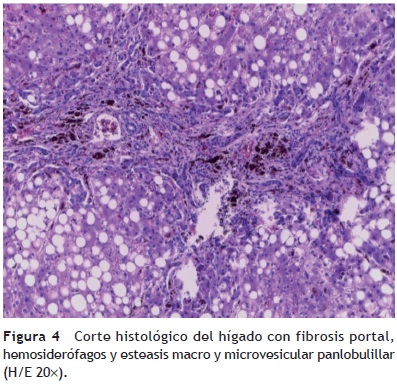

Se encontraron 35 ml de sangre en el hemitórax izquierdo y 25 ml en el pericardio, además de una hemorragia mediastinal. Los cortes histológicos del mediastino mostraron tejido adiposo con hemorragia extensa, restos del timo con corpúsculos de Hassall calcificados y depleción linfoide. Continuando con el mediastino, el corazón tuvo un peso de 100 g vs 115 g. Lo que llamó la atención, desde el punto de vista macroscópico fue una hemorragia petequial en el pericardio, en la aurícula y ventrículos derechos. Visto por su cara posterior se observó la hemorragia en la adventicia de la arteria pulmonar y una hemorragia subepicárdica de 3 × 2 cm. Los cortes histológicos mostraron cardiomiocitos con citoplasma vacuolado, algunos con ligero aumento en el tamaño del núcleo. Esto resulta importante porque la paciente había recibido daunorrubicina, que es cardiotóxico. Sin embargo, no hay cambios histológicos secundarios a la administración de este fármaco. El hígado tuvo un peso esperado de 1600 g contra un esperado de 756 g. Macroscópicamente, se observó un color café claro; histológicamente se observaron muchos cambios, como alteraciones importantes en la arquitectura por la presencia de fibrosis a nivel de las venas centrales, principalmente. A nivel de los espacios porta y de las venas centrales se observaron numerosos hemosiderófagos. En el lobulillo hay esteatosis, y en los sinusoides, también numerosos hemosiderofágos (fig. 4). En el lobulillo, la esteatosis es macro y microvesicular. Estos son datos importantes en la lesión por medicamentos que, al parecer, es lo que se observa en el hígado. La presencia de esteatosis macrovesicular es secundaria a esteroides, y la presencia de esteatosis microvesicular es secundaria a la administración de metrotexate y L-asparaginasa. La fibrosis y el daño que vemos en los espacios porta son secundarios al depósito de hemosiderina tan extenso en esta paciente; además, hay colestasis intracitoplasmática. Se realizó una tinción de Masson donde puede observarse la presencia de puentes de fibrosis, que unen las venas centrales con los espacios porta, dato de lesión irreversible que probablemente progresaría a cirrosis. A mayor aumento es evidente el depósito de colágena IV y VI y la expansión importante a nivel de los espacios porta y de las venas centrales. En una tinción de Perls, específica para ver depósitos de hierro, se puede ver la presencia de hemosiderófagos, con distribución en gránulos gruesos en todos los campos (fig. 5). Resulta importante porque, con base en esto, se realiza la gradificación histológica. Este es un grado IV/IV en la escala de Krause, con presencia de hemosiderina en todos los campos con distribución en gránulos gruesos.

Con estos hallazgos, las alteraciones concomitantes fueron las que a continuación se enlistan:

• Hemorragia subepicárdica de 3 x 2 cm.

• Hepatomegalia (1,600 g vs 756 g).

• Esteatosis macro y microvesicular panlobulillar compatible con daño por medicamentos.

• Fibrosis portal extensa estadio III/IV.

• Hemosiderosis grado IV/IV de Krause.

En dos artículos se hace referencia a la presencia de daño hepático secundario por hemosiderina en pacientes que han sido tratados con múltiples transfusiones, principalmente por LLA. En un estudio, donde se incluyeron 30 biopsias hepáticas, el daño más importante fue la fibrosis12,13.